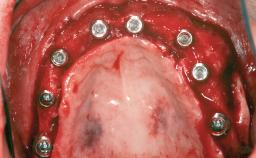

Replacement of Multiple Teeth in a Partially Dentate Posterior Mandible with a Fixed Dental Prosthesis Using a Flapless Approach

An 80-year-old female patient was referred to clinic for rehabilitation of her dentition. The patient’s medical history revealed no significant findings that would preclude routine dental and oral surgical procedures. She reported no drug allergies and was currently taking no prescription medications.

Her chief complaint was her inability to masticate efficiently due to the recent loss of her mandibular second premolars and first molars bilaterally. She expressed a desire for fixed prostheses in the shortest possible time due to her advanced age, requesting that replacement teeth should look as natural as possible. She was otherwise comfortable and not experiencing any symptoms from her teeth.

# of Implants 4

Type of Implants One-Piece|Two-Piece

Guided Surgery Yes